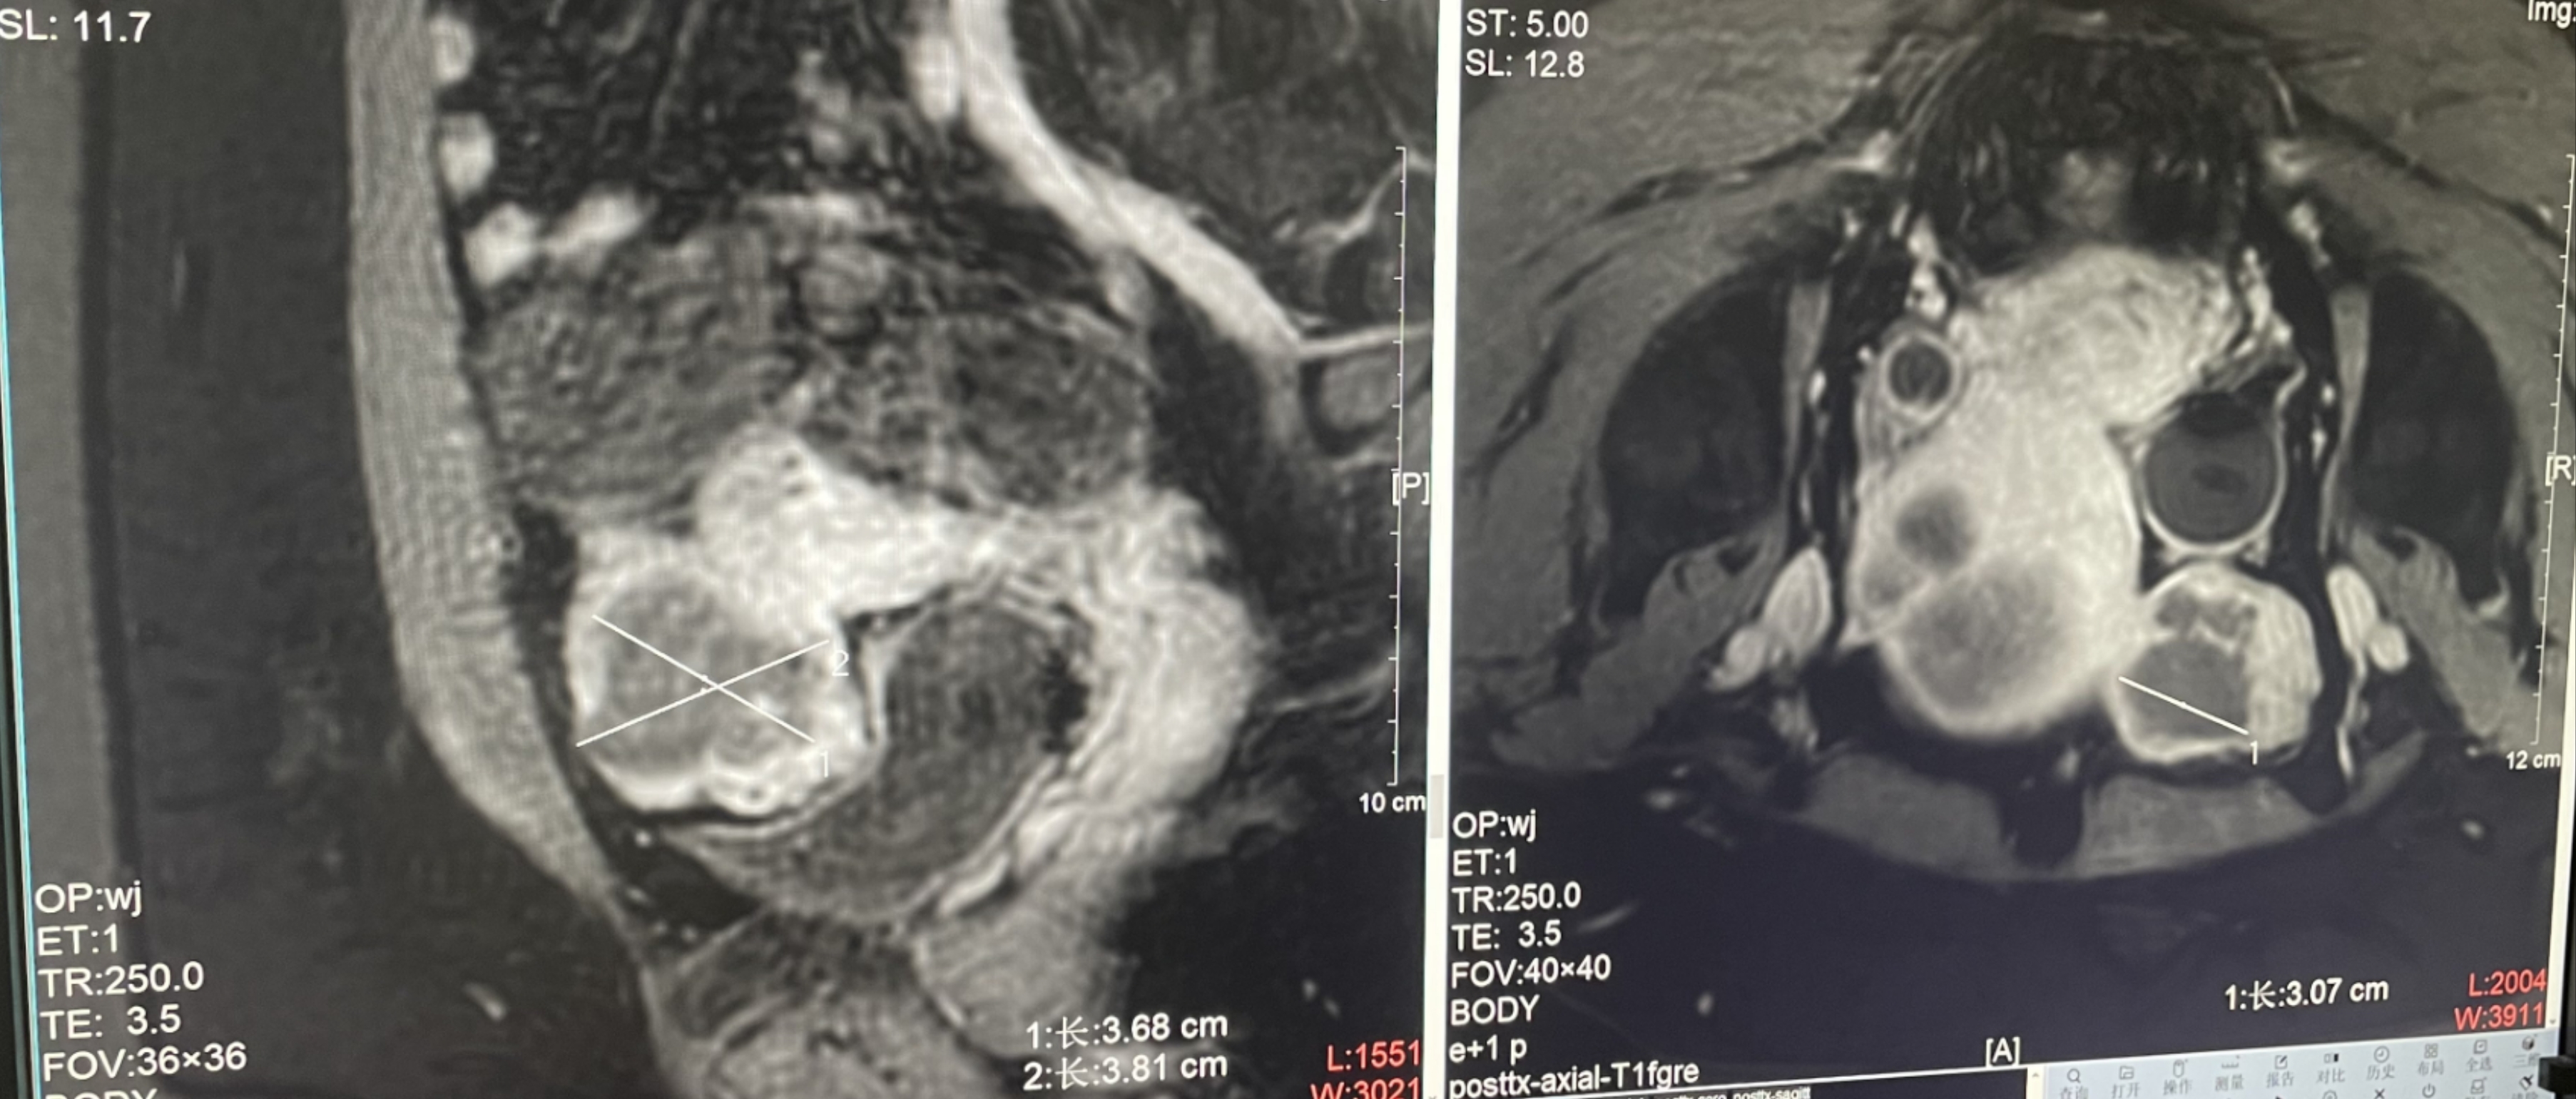

Uterine fibroids

Patient Information:Female,38

Diagnosis: Uterine fibroids

Tumor size: about 38*40*42mm

ROT depth: The ROT center of the tumor is mm from the skin

Postoperative evaluation: Postoperative enhanced imaging showed a good overlap between the ablation area (right) and the tumor area (left), the non-perfusion area was continuous and consistent.

Conclusion:It has a excellent ablation effect on this tumor, and the temperature rise curve during treatment is in line with expectations. The 240CEM area of each treated target is large, full and continuous.The ablation effect was very good,the NPV volume ratio was about 87.88%.